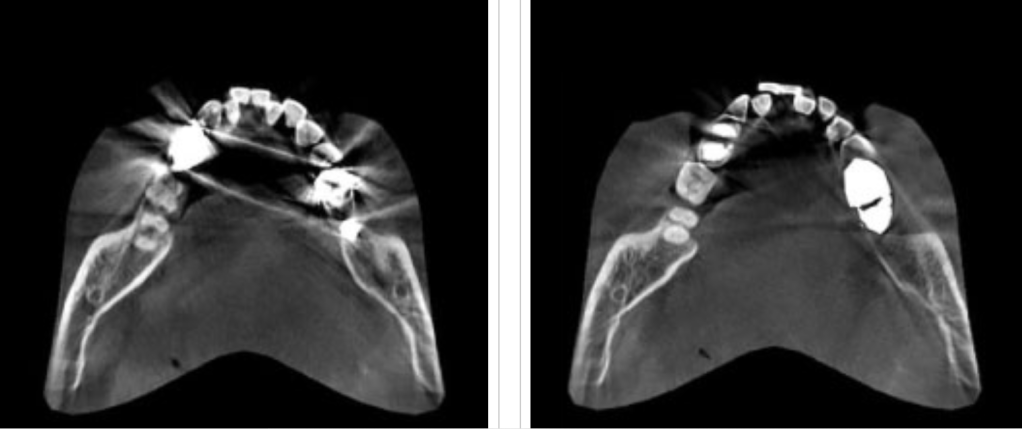

2. ลดการกระเจิงของแสงสำหรับคนไข้ที่มีวัสดุสะท้อนแสงในปากมากๆเช่น อมัลกัม หรือว่าครอบฟัน ทำให้สามารถวินิจฉัยได้ชัดเจนมากขึ้น

3.ด้วยเทคโนโลยี ART-V สามารถมองเห็นในมุมที่ลึกขึ้นกว้างขึ้น ทำให้การรักษา มีความปลอดภัยมากยิ่งขึ้น